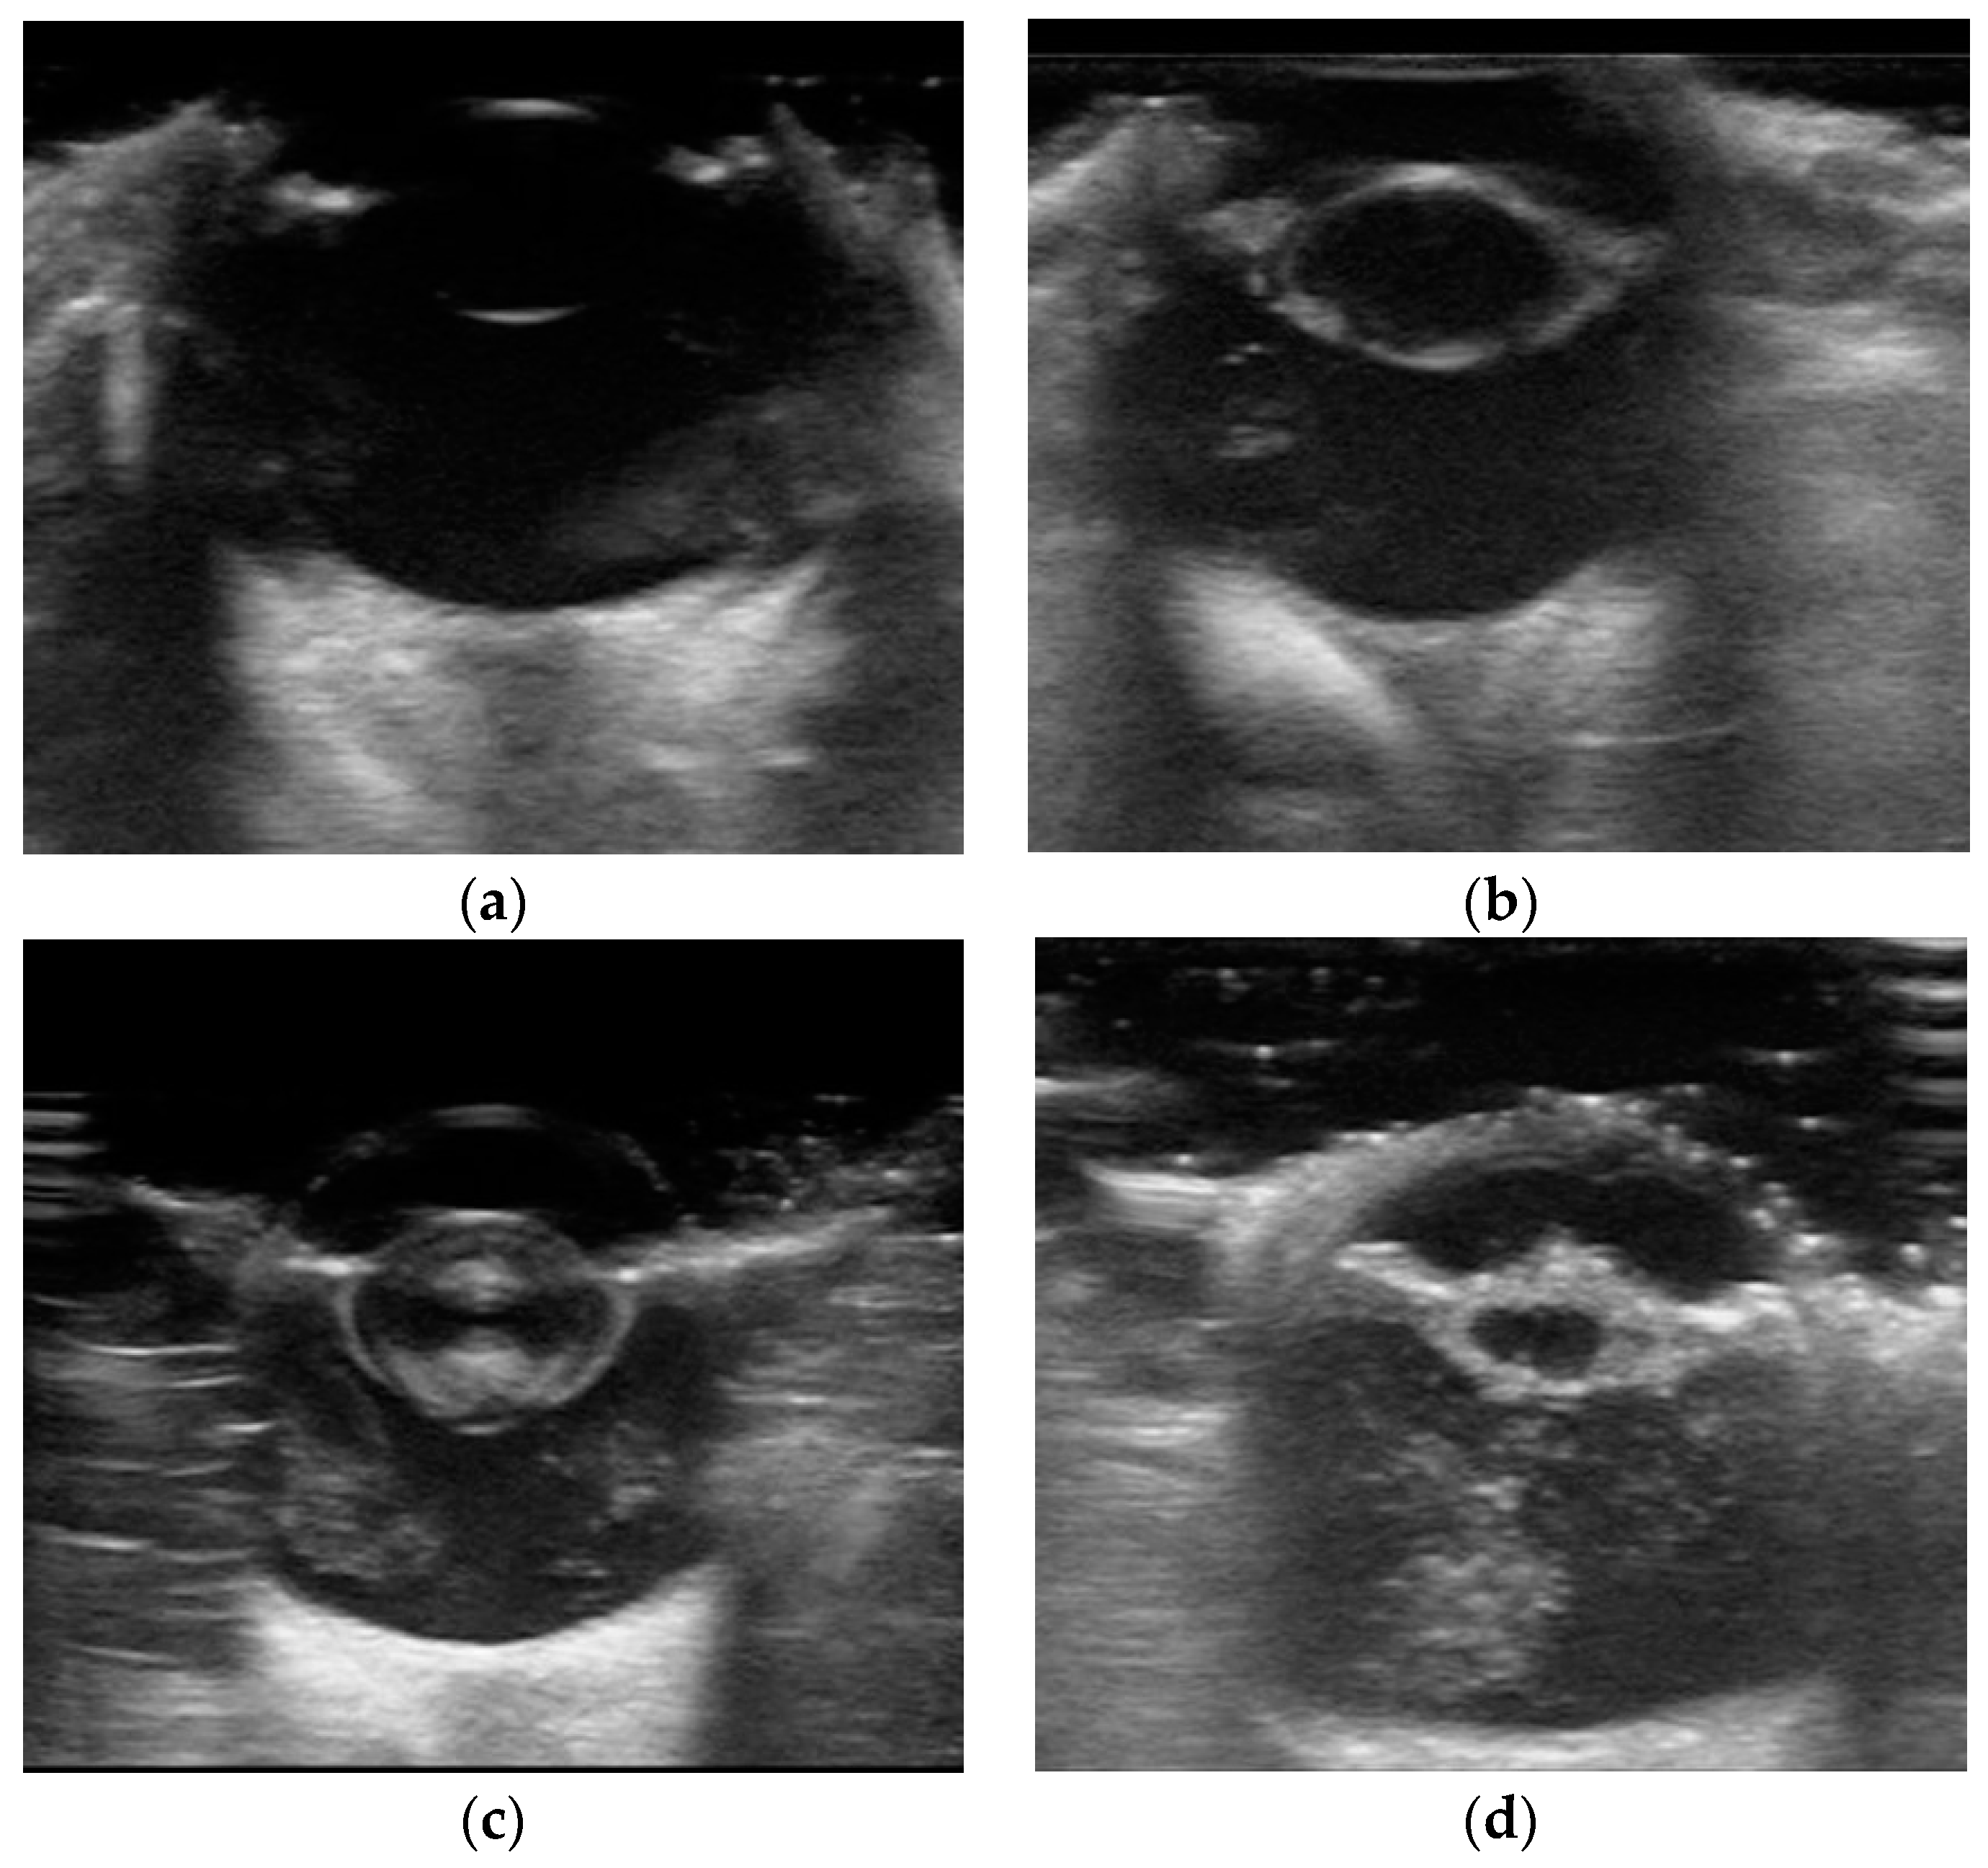

2.1. Datasets